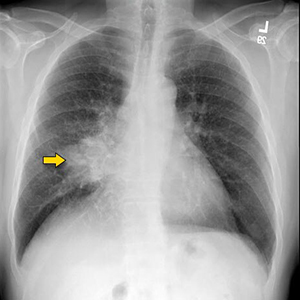

Yes. Your doctor after examining you may advice Chest X-ray. If the chest X-ray is suspicious of lung cancer, he or she will probably follow up with other tests. These can include:

- Blood tests

- CT or PET scan

- Biopsy – May be by bronchoscopy or CT scan guided.